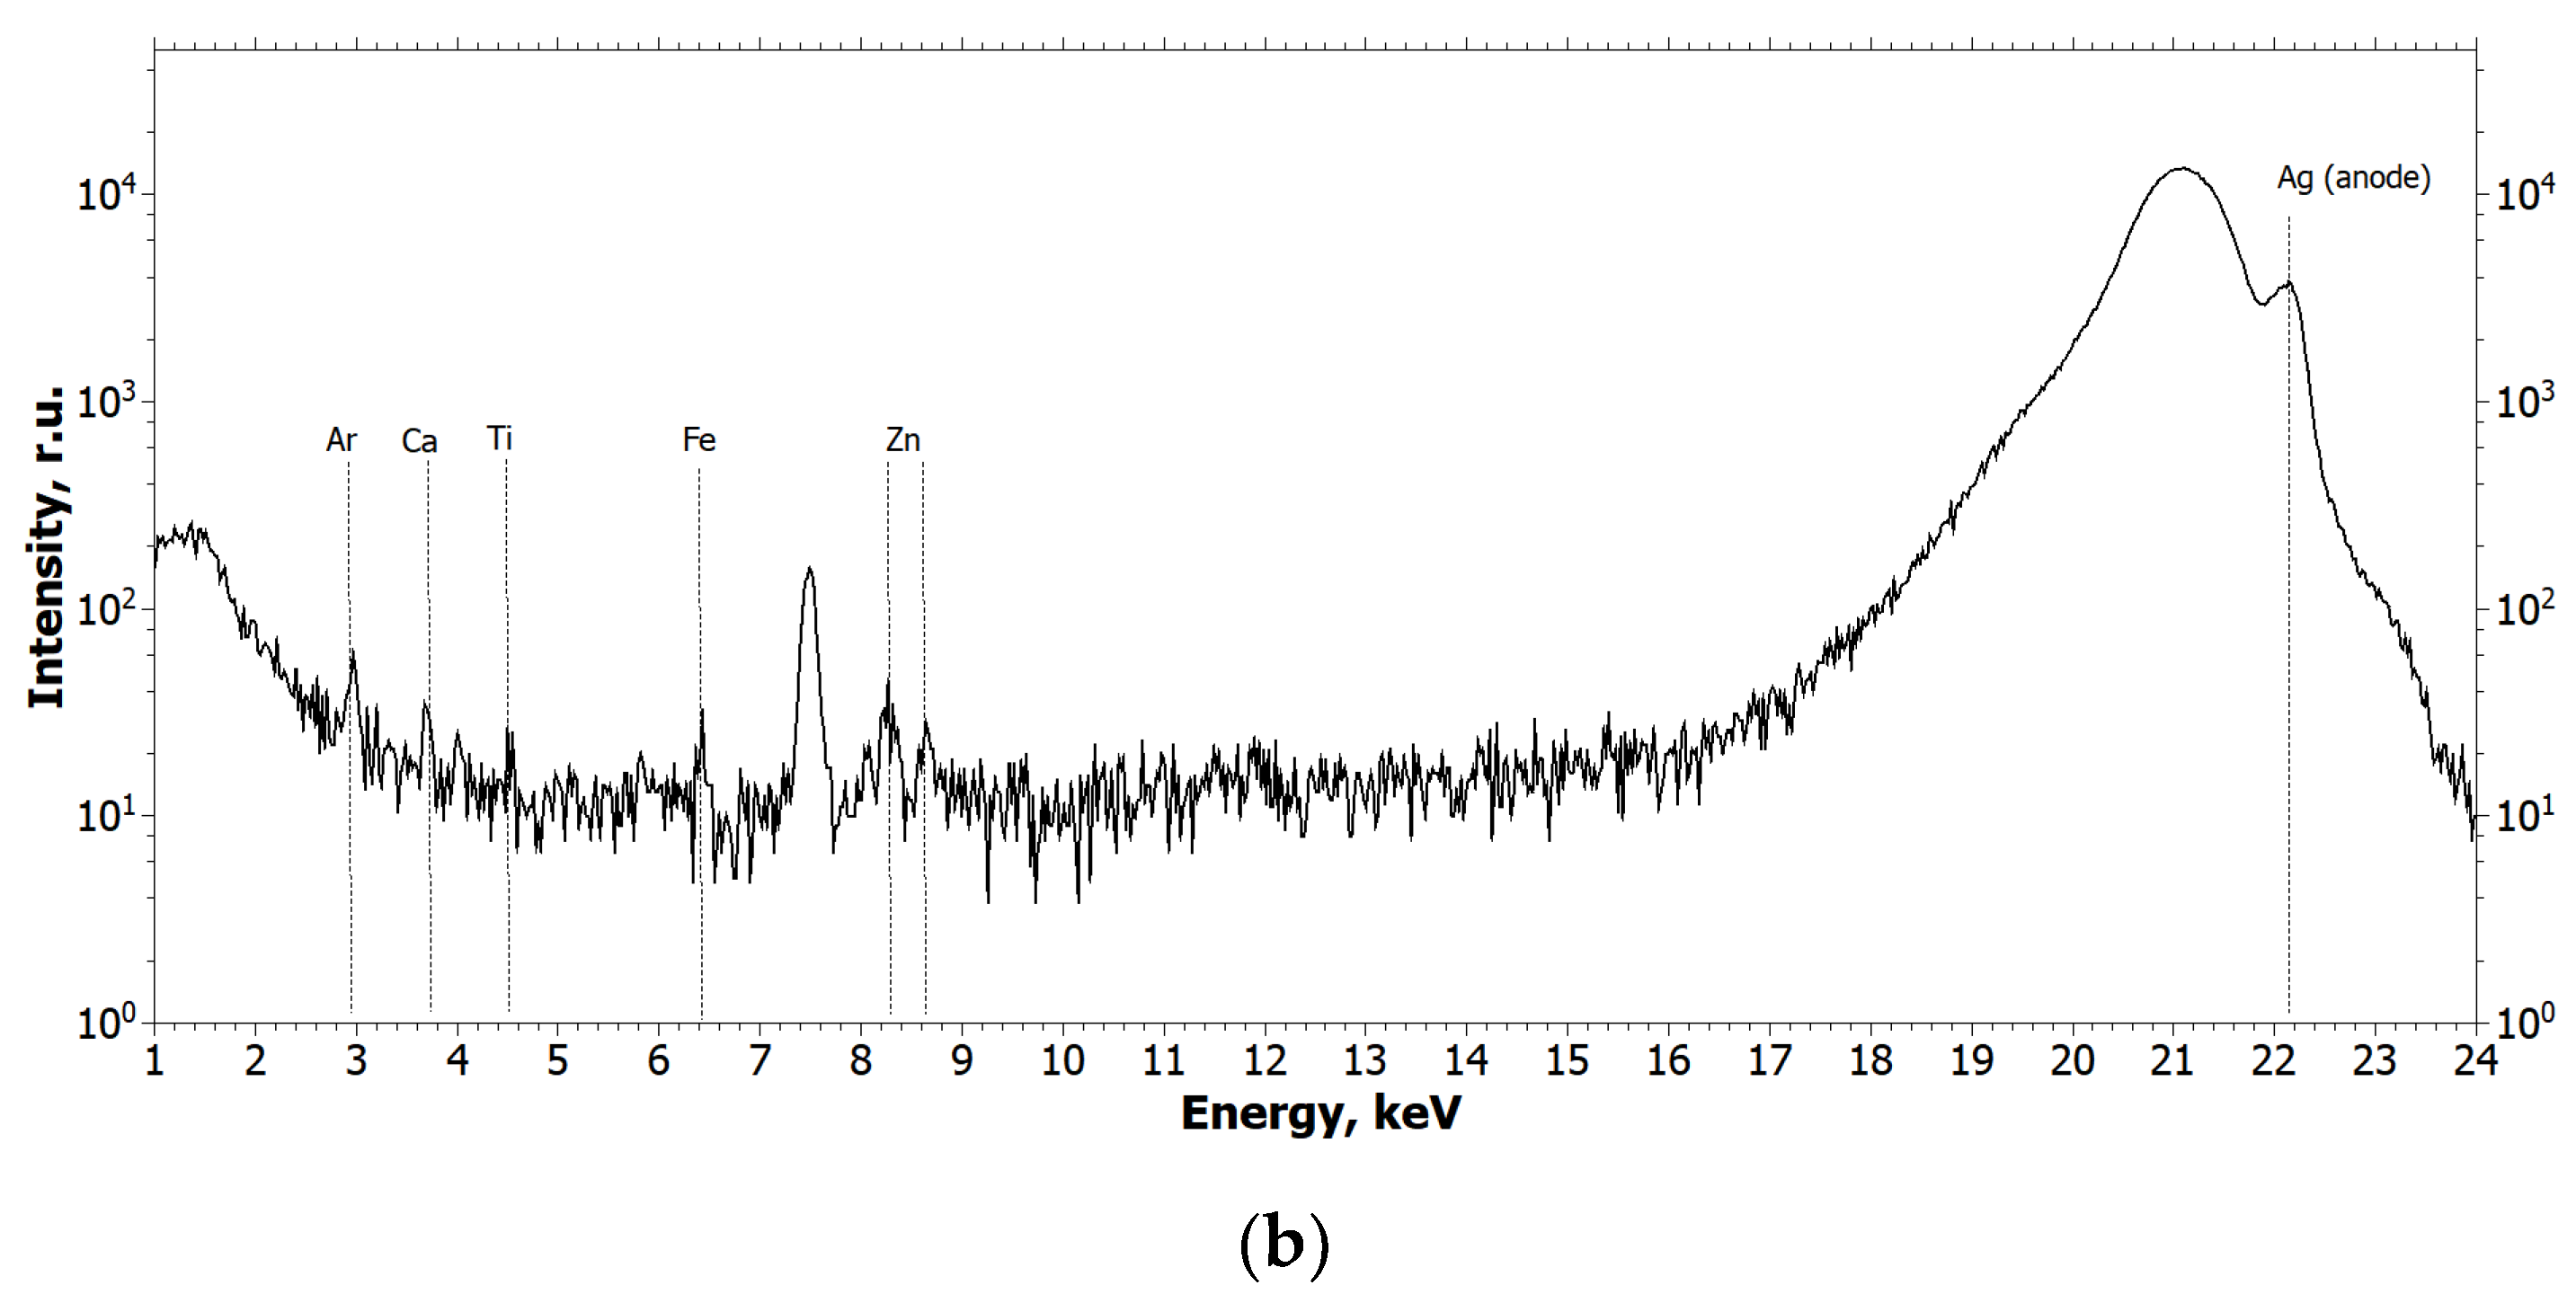

4.3. X-ray Fluorescence Analysis (XRF)

- Ag tube (focus size 10 × 1.0 mm), 40 kV × 40 mA mode;

- Monochromator—silicon (symmetrical), reflection (111);

- Wavelength—0.55 Å (E = 22.162 keV);

- Beam size—10.0 × 1.0 mm (slits adjustable);

- Detector—Amptek 123SDD (Amptek, Bedford, MA, USA);

- Exposure—1200 s per measurement.